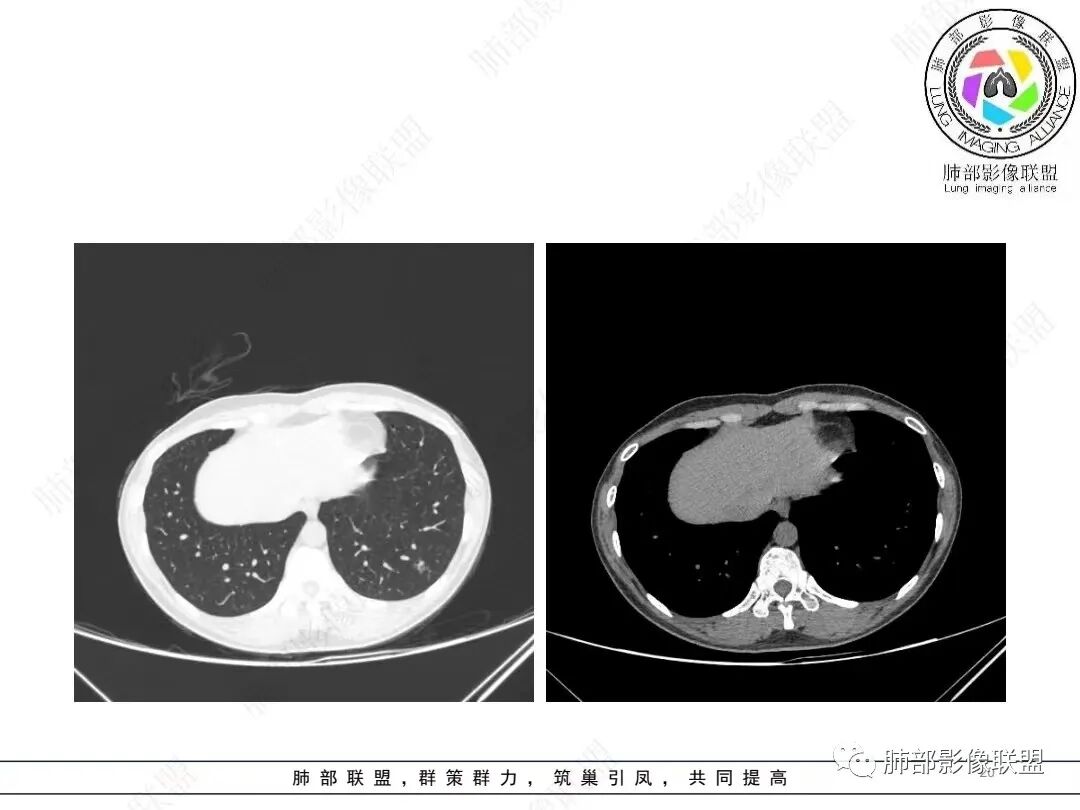

1、临床特点: 37岁女性,体检发现肺结节,2年前有甲状腺腺瘤手术史。实验室无阳性发现。

2、影像特点:左肺下叶类圆形结节影,周围可见多发细小毛刺,浅分叶,张力不高,未见胸膜牵拉。病灶内隐约见空泡影(未提供CT值),近端部分血管呈杵状增粗,可疑脐凹征。增强后实性部分有轻度强化。外围病灶,与支气管关系不明确。